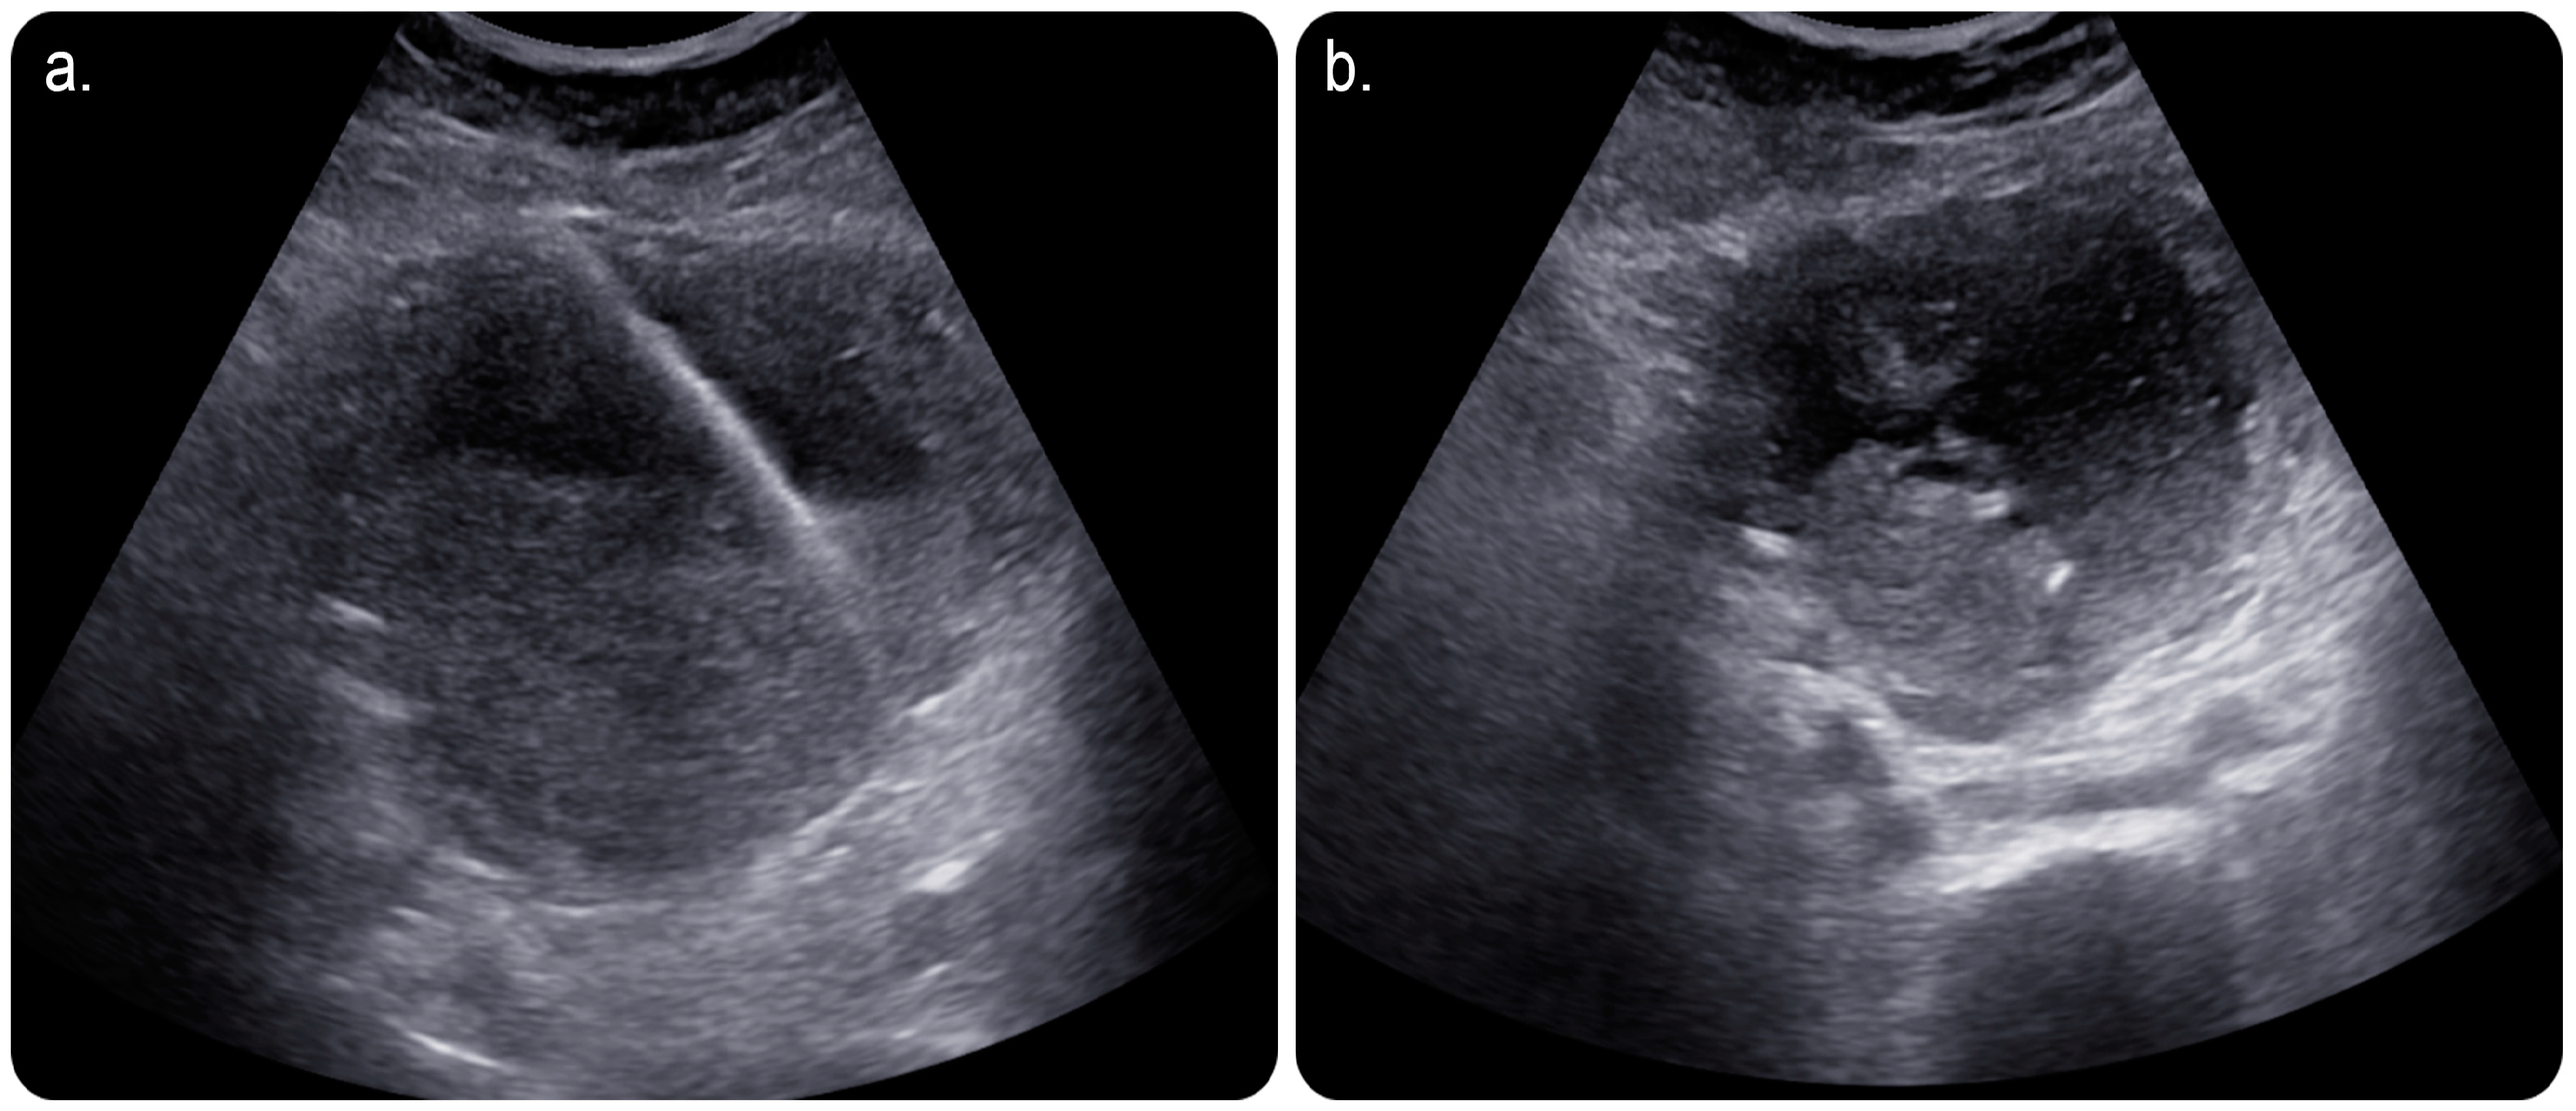

2. Case Presentation